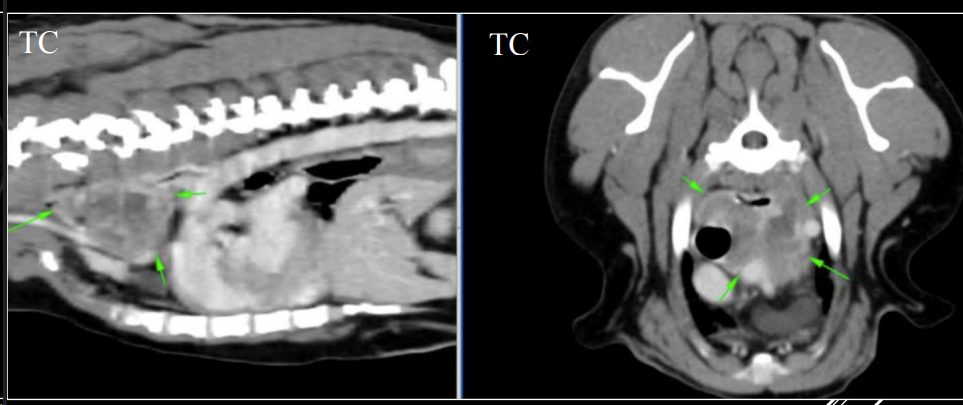

- TOMOGRAFÍA COMPUTERIZADA Nos da mas información que una radiografia, mas cara y necesita anestesia general

APLICACIONES DEL TC

- Siempre empezamos por una radiografia, ya luego tomogrofia o TC (Al ser mas caro y siendo generalmenta la mayoria de problemas diagnosticables con radiografia)

- Exploraciones radiográficas inconcluyentes.

- Ampliar información de estudios radiográficos.

- Diferenciar entre lesión mediastínica, pulmonar, pleural o pared torácica.

- Detectar metástasis de pequeño tamaño o tromboembolismos pulmonares.

- Evaluar la lesión previo a cirugía.

- Toma de biopsias guiada.